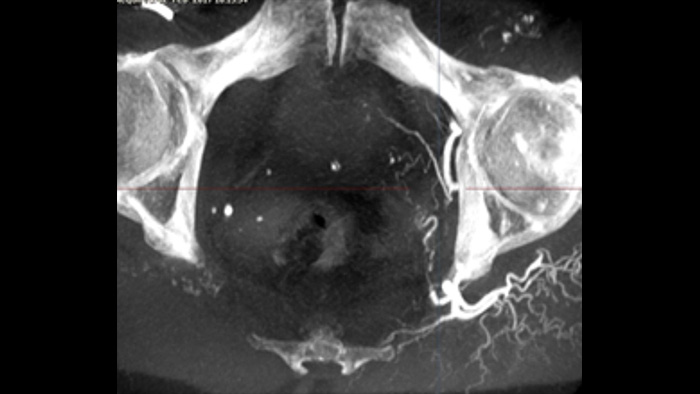

SmartCT Soft Tissue offers a cone-beam CT (CBCT) acquisition technique augmented with step-by-step guidance. Advanced 3D visualisation and measurement tools are all accessible on the touch screen module at table side. You are guided through key steps to support you in acquiring CBCT images first-time-right1 and to streamline your workflow.